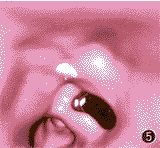

图5 支气管内膜结核病人VB像,显示中间段和下叶支气管钙化灶(白色)